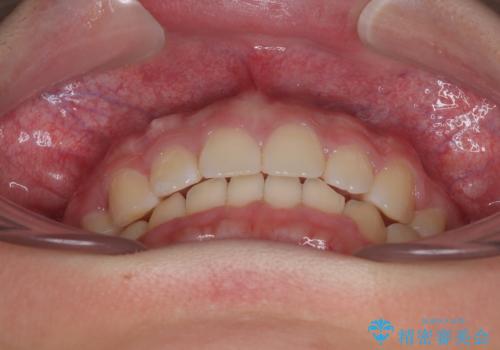

- 上顎前歯が飛び出していて唇がうまく閉じられないとのことで来院された患者様です。

くちばしのように前歯が突出していたため、口元を積極的に引っ込めるために、上下左右の小臼歯4本を抜歯することとしました。

また、上顎歯列が下顎に対して前方位に位置していたため、補助装置を用いて上顎歯列を後方に移動させ、より積極的に口元を下げるようにしました。

上下正中位置を改善するため、左下はイレギュラーに第二小臼歯を抜歯しました。そのため治療期間の長期化が予想されましたが、2年半ほどで期待通りの歯列に仕上げることができました。